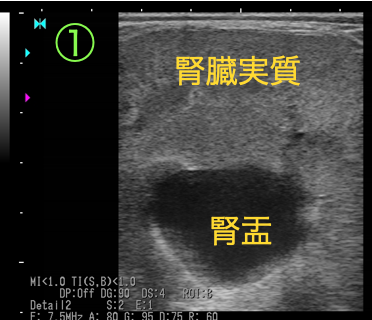

断面②

通常であればエコーで映せないはずの尿管が内腔1cmまで拡張し、壁は肥厚しています。

以上の画像と触診から、腫瘤①が尿管を巻き込むように形成されており、巻き込まれた尿管は著しく狭窄し(③④)、腎盂および腫瘤より腎臓側の尿管は鬱滞した尿により著しく拡張している(①②)ことがわかりました。